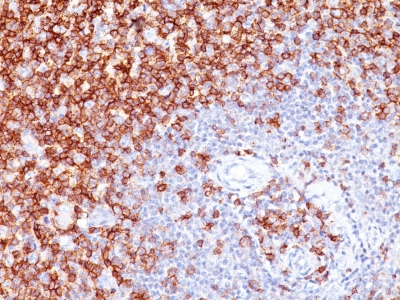

Figure 1: Immunohistochemistry of paraffin-embedded sections (kidney) Figure 1: Immunohistochemistry staining of human kidney (paraffin-embedded sections) with anti-cytokeratin 18 (C-04).

Immunohistochemistry (paraffin sections): Recommended dilution: 10 μg/ml; positive control: colon, kidney.